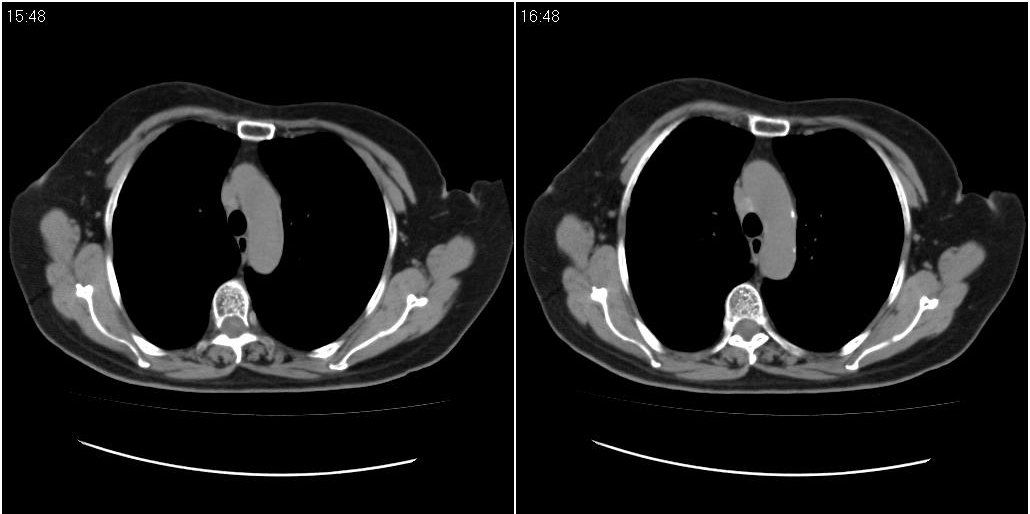

女性,72岁。去年9月份发现肺部病变,诊为肺结核并进行正规治疗至今,但复查后发现ct表现几乎没有变化。

右侧中叶支气管明显狭窄,建议行纤支镜检查!

右中间段支气管局限性狭窄,右中叶支气管亦稍显狭窄,但并未见明显占位表现,半年多了,无变化也许是好事,可能为炎性狭窄,建议继续随访。

双肺继发型tb并右中叶内膜tb,轻度支扩,左下胸膜肥厚粘连。

右中叶炎性改变,支气管狭窄但较光滑,占位可能性不大。

右中间段支气管局限性狭窄,右中叶支气管亦稍显狭窄.

双肺继发性肺结核并右肺中叶节段性肺不张,左下胸膜肥厚粘连。

右肺中叶节段性肺不张,考虑结核或慢性炎症,建议做纤支镜检查。

双肺继发性肺结核并右肺中叶节段性肺不张